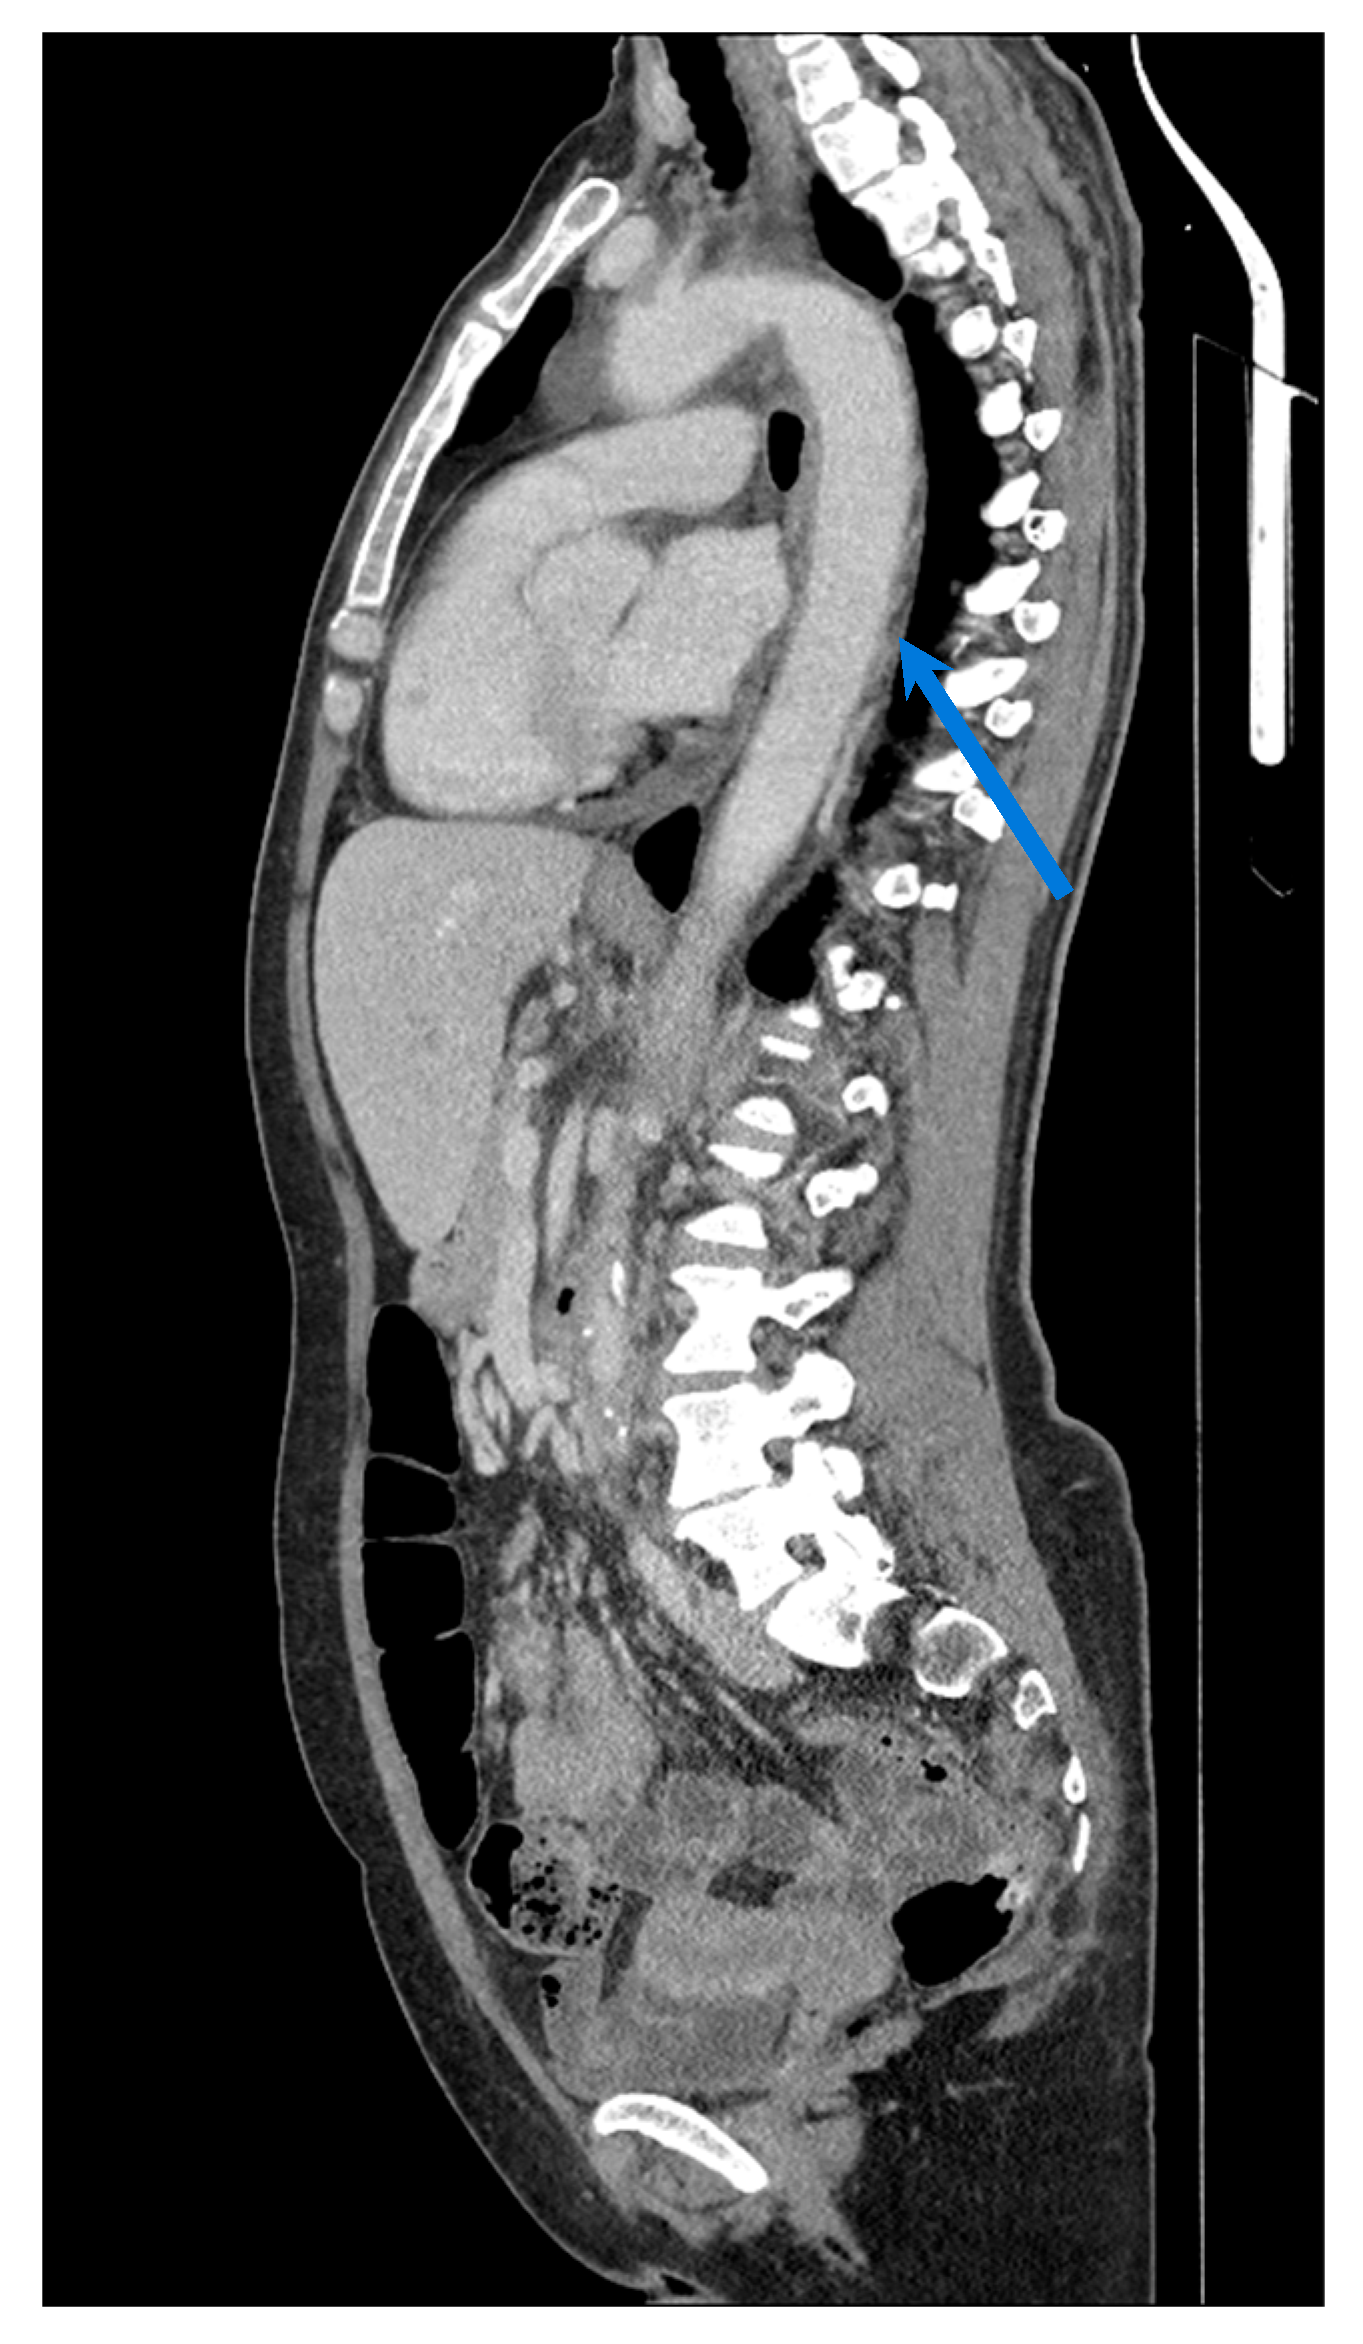

| CT/CTA | High; wide anatomic coverage. | High for vascular structural characterisation; poor for inflammatory changes. | Better suited for evaluating chronic vascular damage rather than active inflammation. | Widely available; rapid acquisition time; enables anatomic mapping. | Ionising radiation; use of iodinated contrast; limited ability to detect active inflammation. |